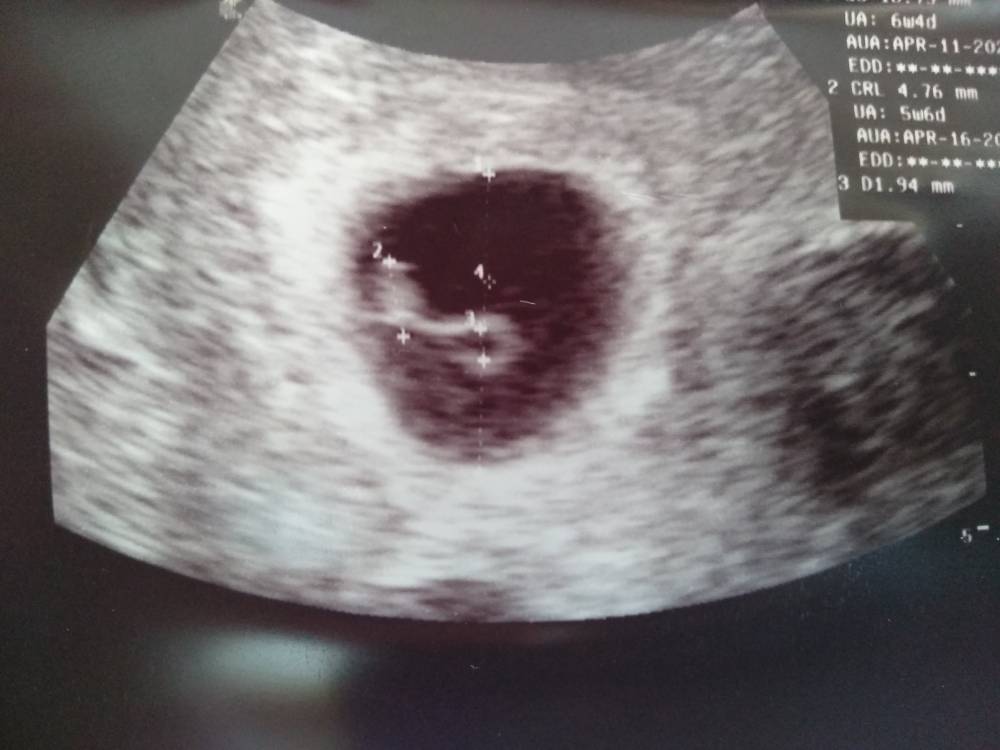

No to ja zacznę pierwsza. Wszystko ok! [emoji3526] Jest akcja serca, zero śladów jakichkolwiek krwawień. Niepotrzebna panika.